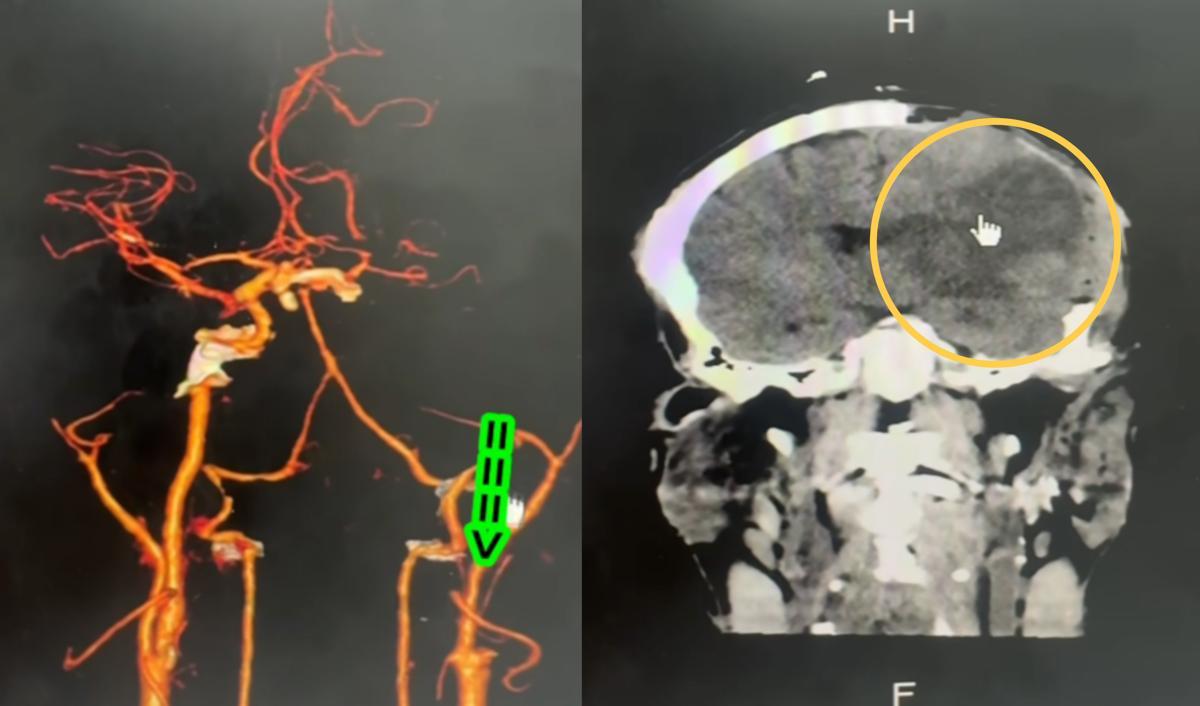

병원에 도착했을 때는 이미 뇌 손상이 진행된 상태였다. CT 검사 결과, 왼쪽 뇌는 이미 산소 부족으로 괴사한 상태였다. 또 경동맥(목에서 뇌로 가는 큰 혈관) 두 곳이 손상된 것으로 확인됐다.

마사지로 인해 혈관이 파열됐고, 혈전이 생겨 혈류를 막아버린 것이다. 그 결과 뇌에는 8시간 동안 혈액이 공급되지 않았다. 이후 경동맥 손상은 순식간에 뇌졸중으로 이어졌다. 남성은 결국 사망했다.

프라차는 “경동맥이 지나가는 목 앞을 잘못 누르면 혈관 벽이 찢어져 그 안으로 피가 스며들고, ‘경동맥 박리’가 생겨 결국 막히게 된다”며 “전문적인 지식 없이 목을 주무르면 장애는 물론 사망에 이를 수 있다”고 강조했다.